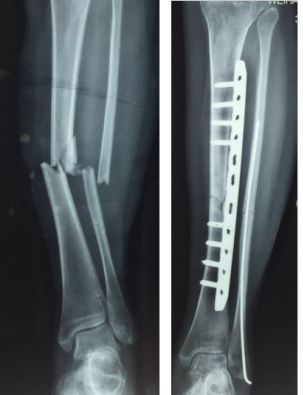

两处腓骨钢板多余(因为下胫腓骨联合没有损伤,特别注意不要犯这种错误)(髓内钉加阻挡钉首选,其次内侧长钢板,如果没有钢板用外固定架也可以)

胫骨远端简单骨折选用钢板固定没有实现坚强固定,钢板承受应力,孔处应力集中断裂

更换长钢板后愈合